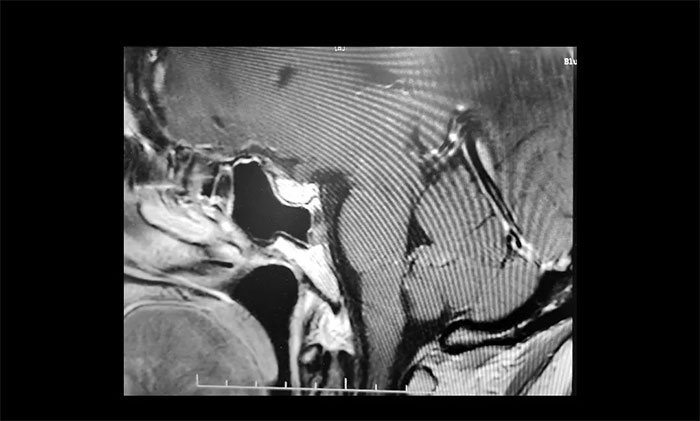

術中,在蔡司顯微鏡(雙熒光)下,見腫瘤組織包繞左側嗅神經,雙側視神經被生發(fā)于鞍結節(jié)處的腫瘤組織擠壓至外下方,且與腫瘤組織關系密切。李士其教授處之泰然,在充分保護好重要血管神經的前提下,逐步將腫瘤與周圍的神經、血管一點點分離開來,分塊切除腫瘤,讓視神經得到了充分減壓。歷時3個多小時,手術終于順利完成。

▲ 術后影像顯示腫瘤被切除